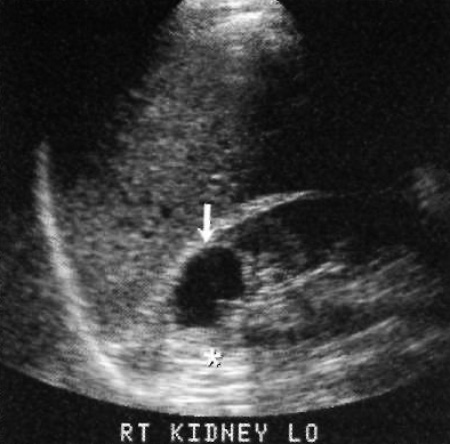

Простая киста на УЗИ определяется как анэхогенный просвет с четкими тонкими и гладкими стенками, отмечается заднее усиление сигнала, возникновение которого обусловлено более быстрым прохождением ультразвука через жидкость, чем через мягкие ткани. Таким образом позади жидкостной кисты возникает сигнал большой амплитуды (фото 12).

Фото 12. Киста почки. Стрелкой обозначена простая киста, которая представляет собой анэхогенное образование с четко визуализируемой задней стенкой и акустическим эффектом усиления (обозначен звездочкой)